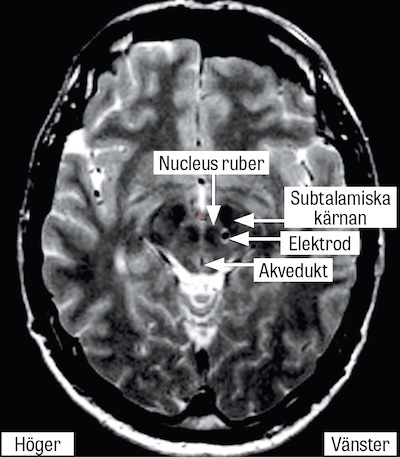

Stereotaktisk neurokirurgi inbegriper normalt att en stereotaktisk ram fästs på utsidan av skallbenet (tabula externa) med fyra skruvar. En DT/MR-låda fästs på ramen, och efter radiologisk undersökning erhåller man ett kartesiskt koordinatsystem och kan via ett borrhål föra in elektroder till centrala delar av hjärnan med millimeterprecision. Den första stereotaktiska ramen för människor introducerades 1947, och stereo­taktiska lesioner, framför allt pallidotomi och talamotomi, var före introduktionen av levodopa i slutet av 1960-talet den enda säkra och effektiva behandlingen mot motoriska besvär av Parkinsons sjukdom [1]. Mot slutet av 1980-talet utvecklades djup hjärnstimulering [2, 3], som innebär att stereotaktiskt inlagda hjärn­elektroder kopplas till en stimulator under huden på bröstkorgen. Denna kan därefter programmeras med en extern enhet så att de patologiska signaler som ger upphov till patientens symtom störs ut (Figur 1). De vanligaste anatomiska målen för djup hjärnstimulering är nucleus subthalamicus vid Parkinsons sjukdom, ventrolaterala talamus vid essentiell tremor och globus pallidus internus vid dystoni. Den stora fördelen med djup hjärnstimulering jämfört med tidigare lesionella metoder är att man säkrare kan utföra bilateralt ingrepp, som ofta är nödvändigt vid till exempel Parkinsons sjukdom och dystoni [4]. Behandlingen är komplex, livslång och ställer stora krav på en bred kompetens, varför behandlingen ges av multidisciplinära team. Djup hjärnstimulering  övervägs vid Parkinsons sjukdom hos patienter i komplikationsfas och ökar tiden som patienten befinner sig i sitt bästa motoriska tillstånd (så kallad »good on«-tid), utan tremor, brady- eller hyperkinesier [5]. Djup hjärnstimulering  är i dag en etablerad och evidensbaserad behandling, som enligt Socialstyrelsens nationella riktlinjer för Parkinsons sjukdom ska utgöra förstahandsvalet bland de avancerade behandlingarna [5]. Trots detta skiljer sig Sverige något från andra länder i EU genom att den vanligaste indikationen för djup hjärnstimulering inte är Parkinsons sjukdom utan essentiell tremor. Orsaken är förstås multifaktoriell, men delvis avspeglas detta i att färre av de lämpade patienterna med Parkinsons sjukdom får djup hjärnstimulering i Sverige till förmån för läkemedelspumpar eller fortsatt eventuellt ineffektiv läkemedelsbehandling.

Figur 2. T2-viktad axial MRT-sekvens, som visar en elektrod för djup hjärnstimulering belägen i subtalamisk vitsubstans hos en patient med essentiell tremor.